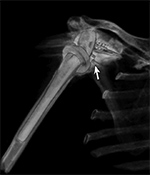

Figure 1 A Figure 1B Figure 2A Figure 2B

Streak artifact Streak artifact Hardware attenuation Hardware attenuation

Streak and Shadow Artifact. (A) Axial CT image of the lumbar spine demonstrates extensive high attenuation linear streak and splay artifact secondary to posterior spinal fusion hardware.  (B) Axial CT image of the left hip demonstrates linear low attention shadow artifact propagating along the axis of greatest metal cross-section, which obscures the femoral neck.

Variable Hardware Attenuation. (A) CT scout image demonstrates heterogeneous density of glenoid components of reverse total shoulder arthroplasty. (B) Axial CT image shows metallic glenosphere (curved arrow) positioned appropriately on less dense metaglene (straight arrow)